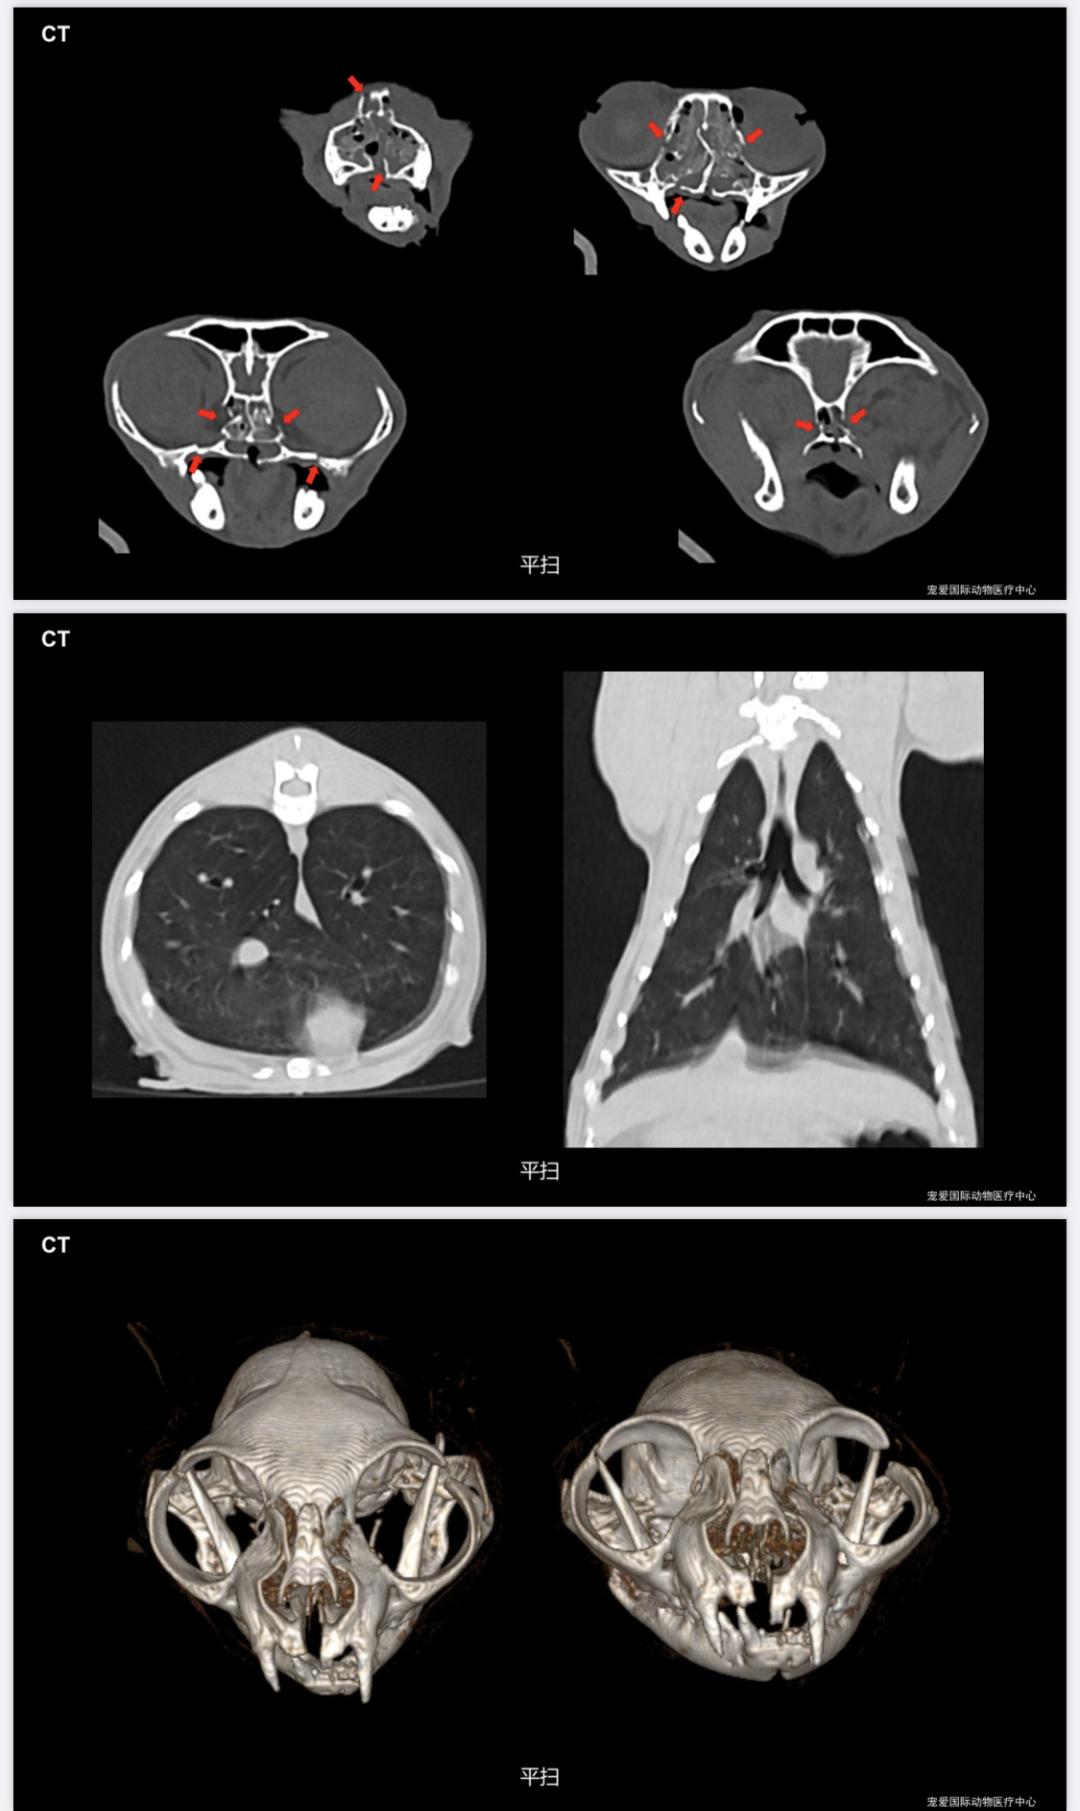

胸腰椎、四肢未见明显骨折;面部、鼻腔、多处骨折。

4.转诊中心医院CT 检查

面部多处骨折、腭裂、贫血

法斗呼吸不畅、运动不耐受,通过CT扫查发现鼻咽部息肉、软颚肥厚↓↓